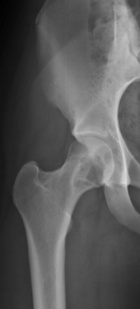

16 year old WF with eight months of right hip and groin pain, hip gives way and pain worsening

Zoom image: Radiological image Radiological image.